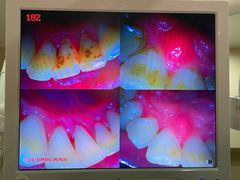

• 土豆口腔(凤凰北总店)

• -土豆口腔(凤凰北总店)